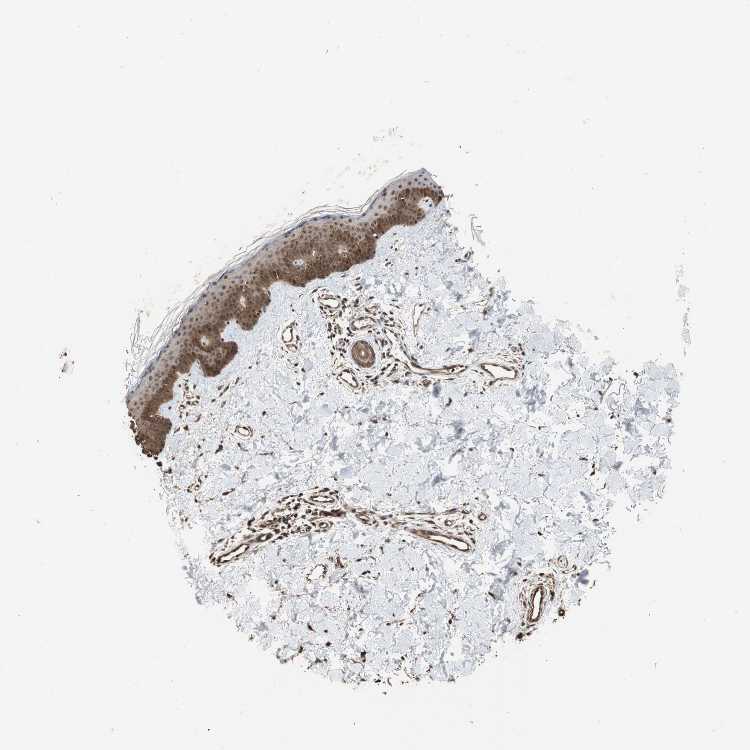

SKIN 1 - Antibody stainingi

Antibody staining in the annotated cell types in the current human tissue is reported as not detected, low, medium, or high, based on conventional immunohistochemistry profiling in selected tissues. This score is based on the combination of the staining intensity and fraction of stained cells.

Each image is clickable and will lead to virtual microscopy that enables deeper exploration of all samples and also displays staining intensity scores, fraction scores and subcellular localization as well as patient and tissue information for each sample.

Antibody HPA006302Antibody HPA011361Antibody CAB012275

Langerhans HighMediumMedium

Fibroblasts MediumMediumMedium

Keratinocytes HighMediumMedium

Melanocytes HighMediumMedium

SKIN 2 - Antibody stainingi

Epidermal cells HighMediumMedium